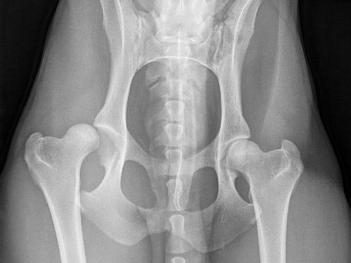

Hip Dysplasia

Canine hip dysplasia is a common cause of lameness and pain in dogs with various medical and surgical management options available. Read more for details on the diagnosis and treatment of hip dysplasia in pets.